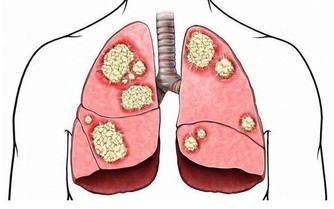

鉀與鎂和鈣一起控制細胞中的液體。如果沒有足夠的鉀,會形成積液,血管壁會收縮,反過來又會導致血壓升高。低鉀也會導致心悸、心律不齊,並在極端情況下引發心臟驟停。一些試驗表明,補充鉀可以幫助平衡血壓,但是不建議大家自行服用高鉀補充劑,因為這可能是非常危險的,如果想服用請遵醫囑。